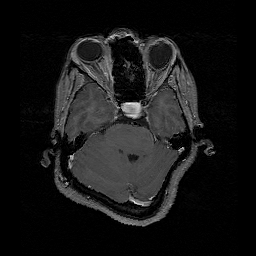

o1.png és o2. png bemeneti képek. A második az első kép mesterségesen TPS pontalapú transzformációval deformált változata.

B-Spline regisztráció eredménye. Csak kisebb mértéke eltérés marad a képek között.